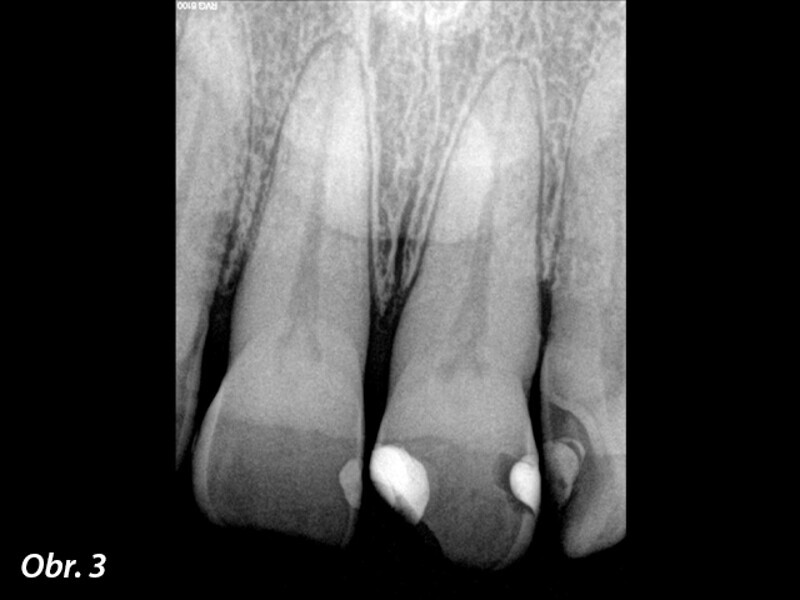

Jednoduchá souhra odstínů k vytvoření opticky harmonické výplně